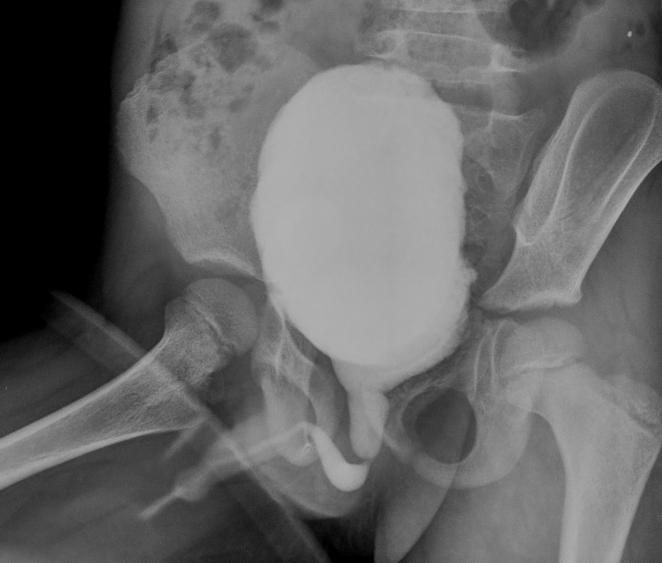

Puzzle 67

What's the Diagnosis?

Guess 1 / 5